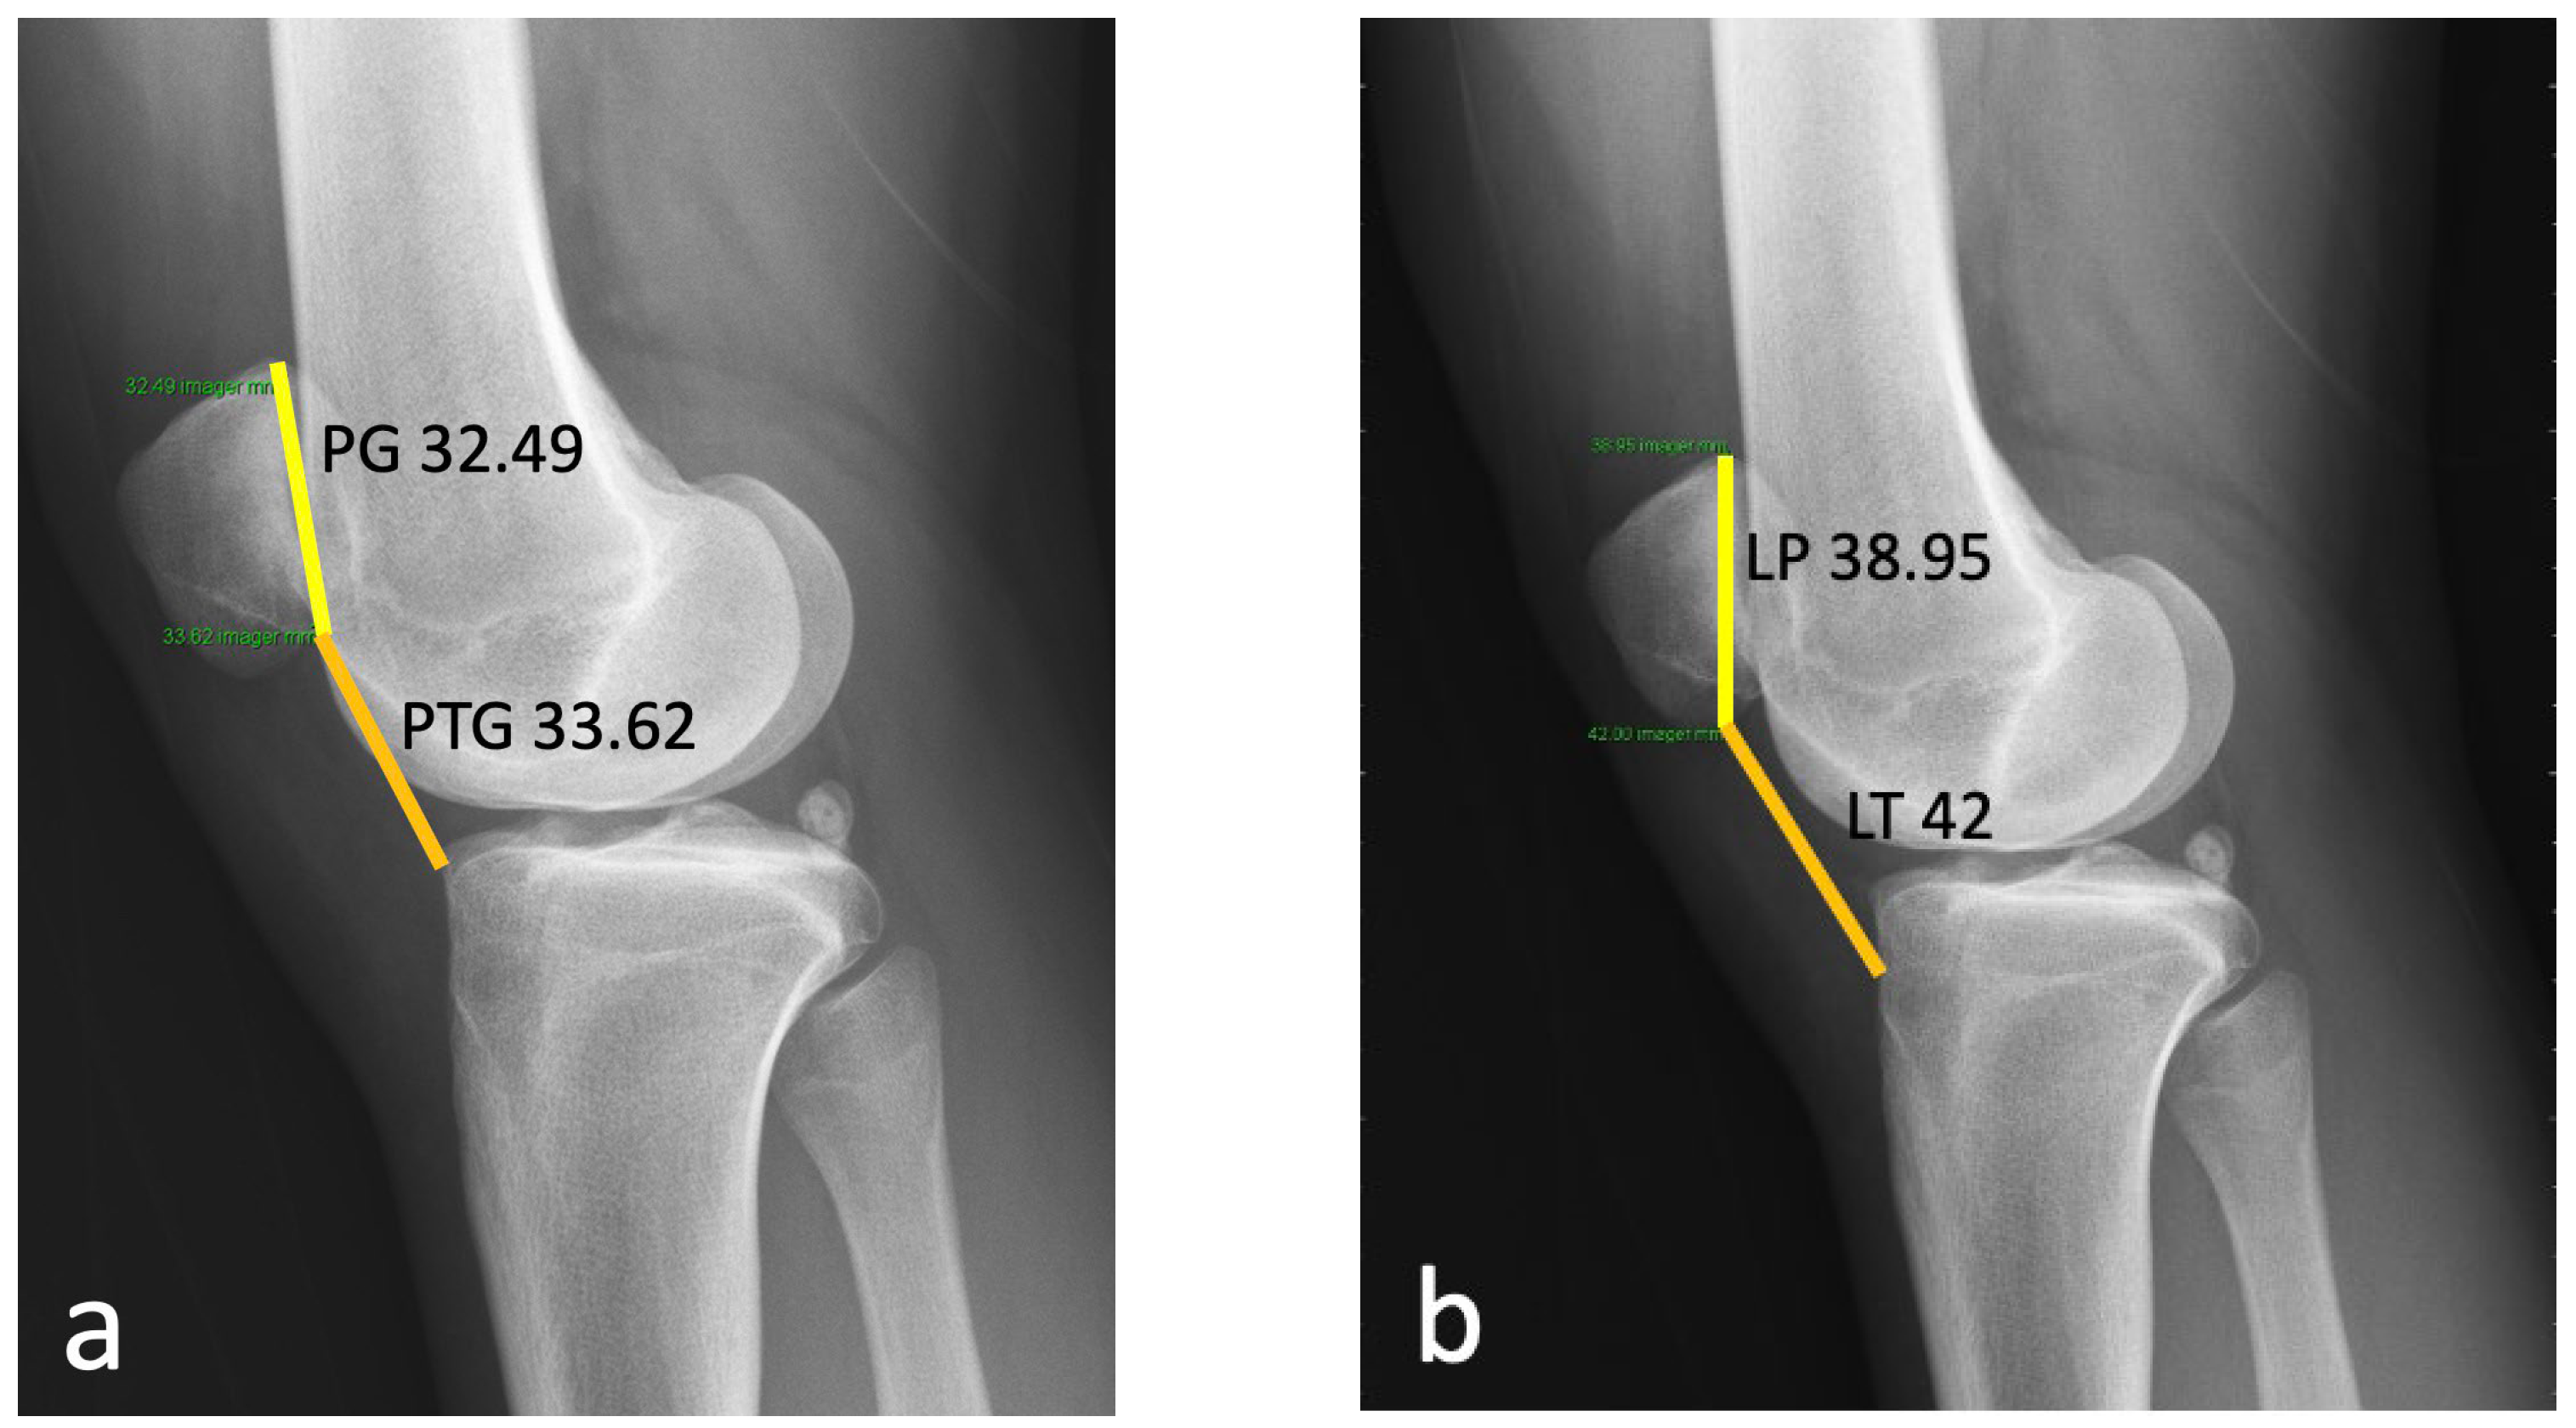

2.1. Case

3.2. Patella Alta

3.3. TT–TG Distance

3.4. Lateral Patella Tilt